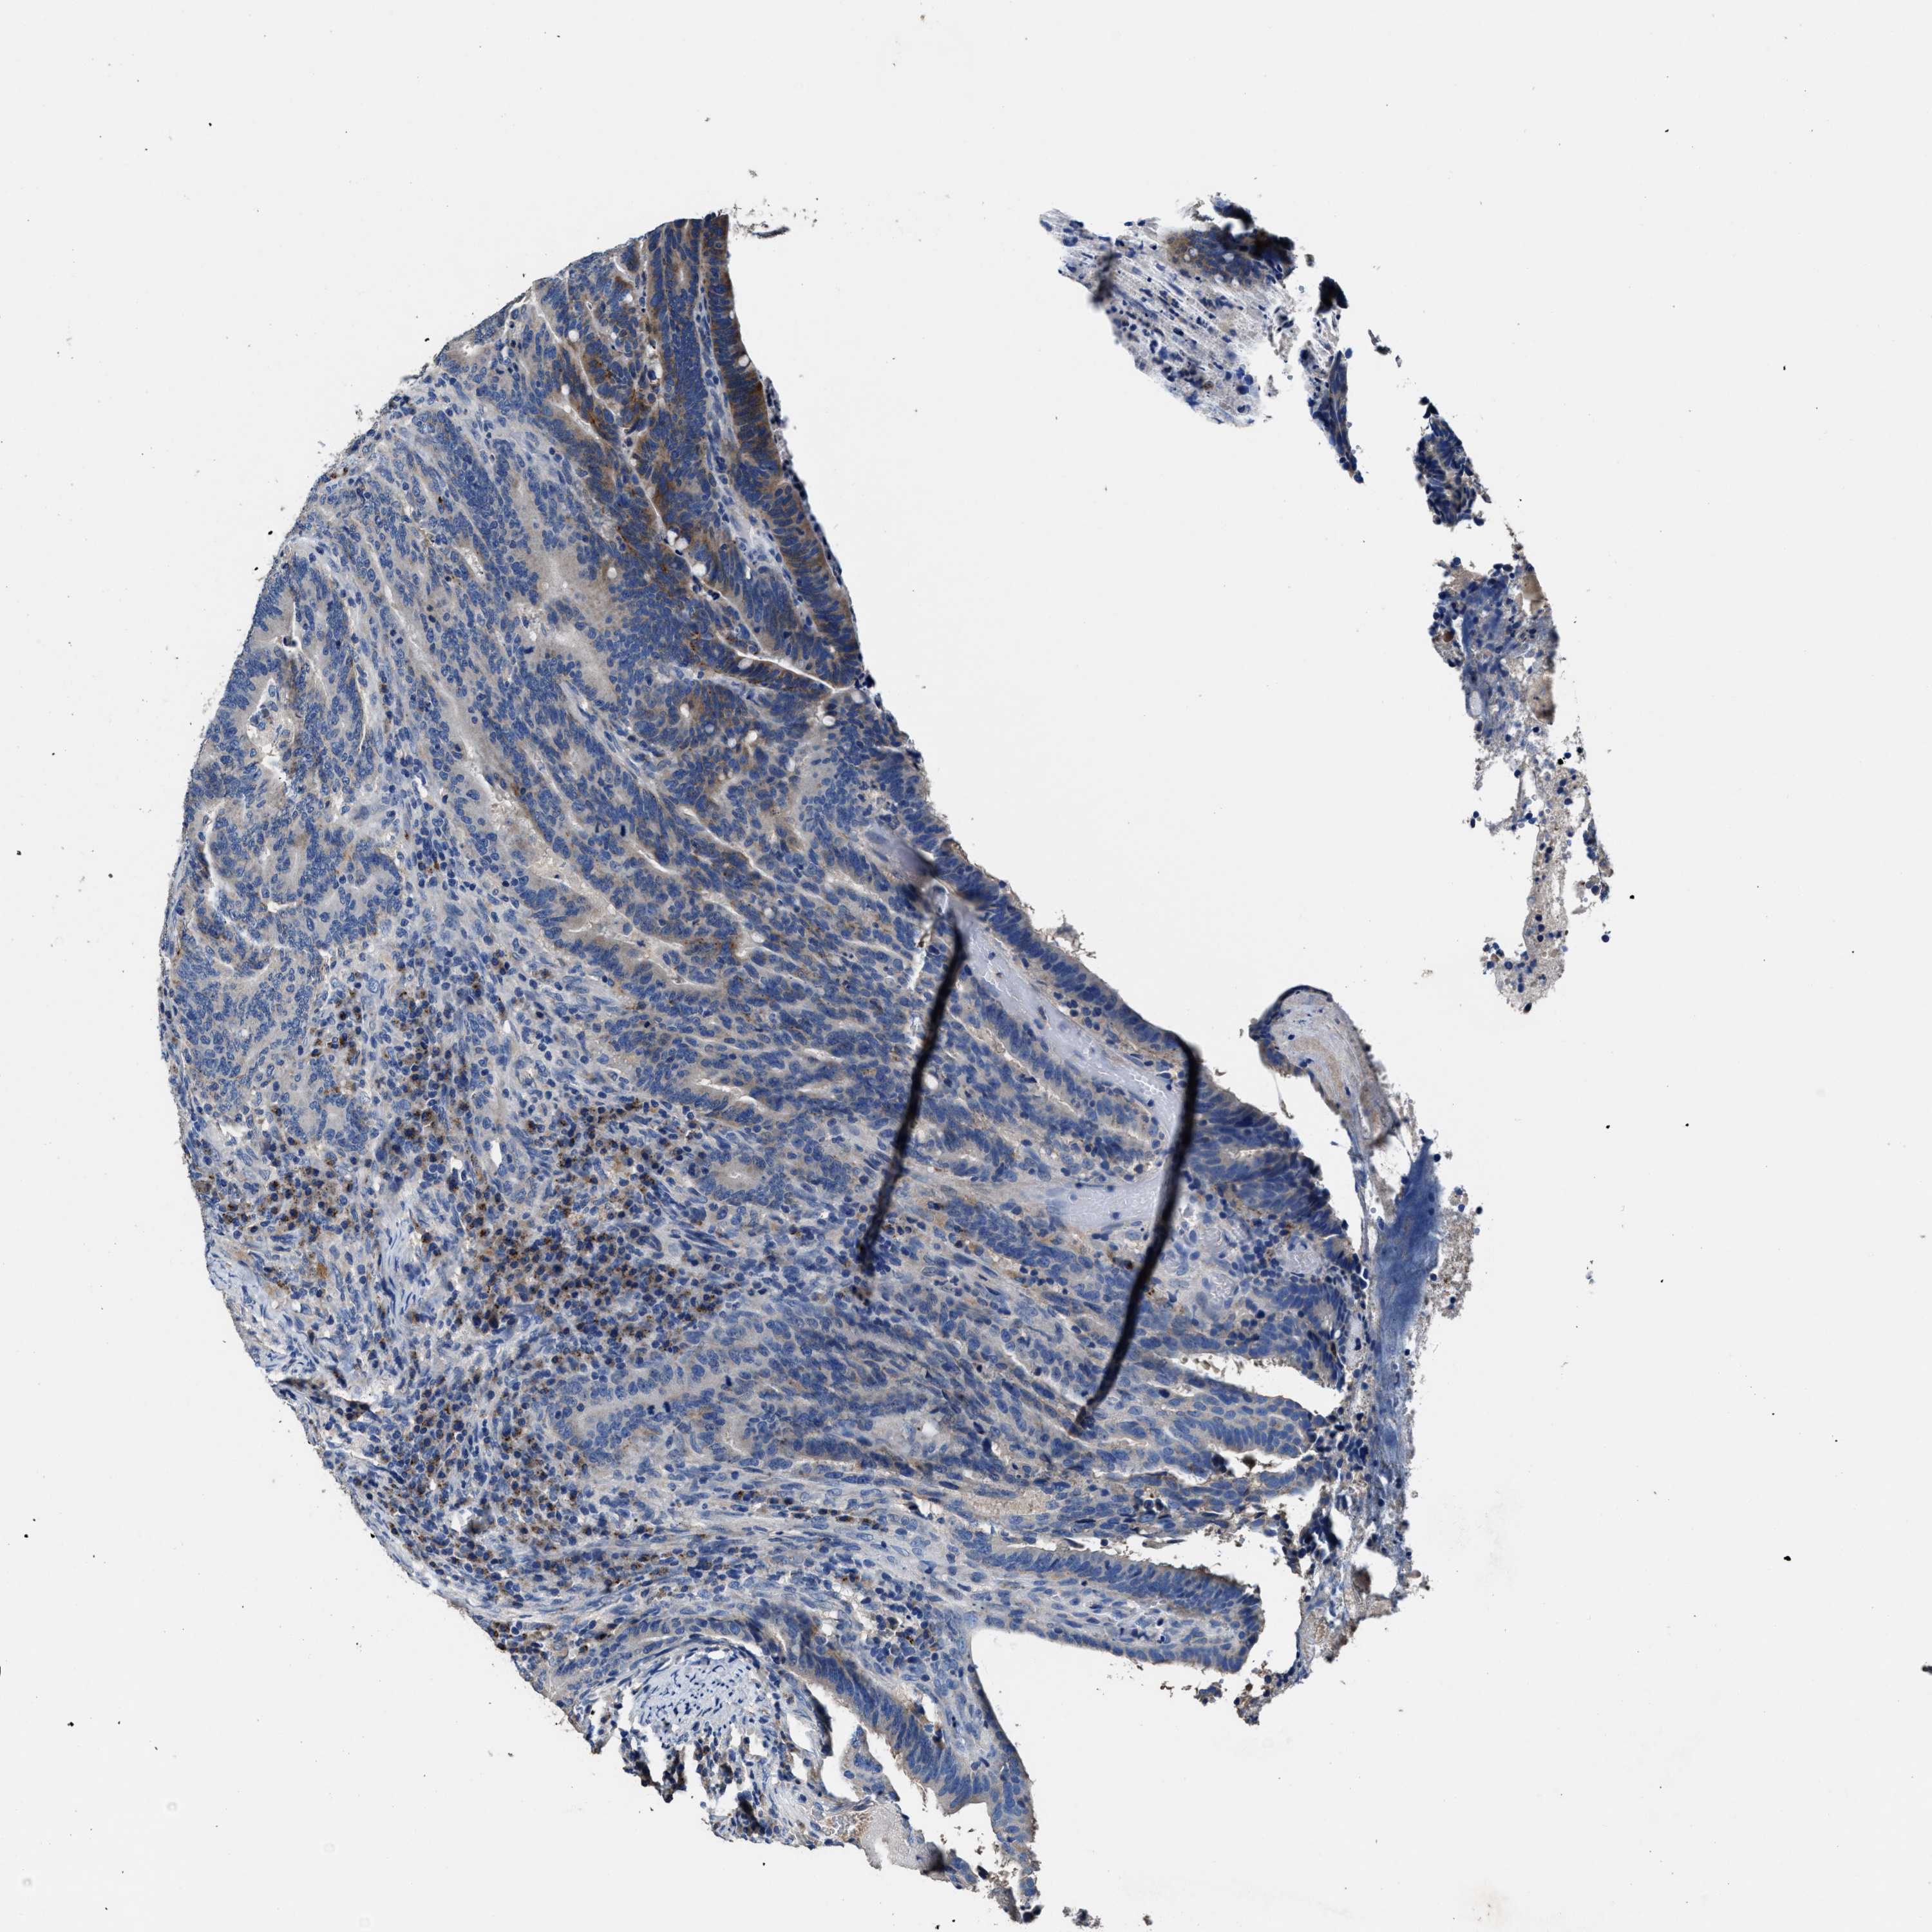

CANCER COLORECTAL CANCER Show tissue menu

Colorectal cancer

Human cancer

Colon adenocarcinoma

Rectum adenocarcinoma